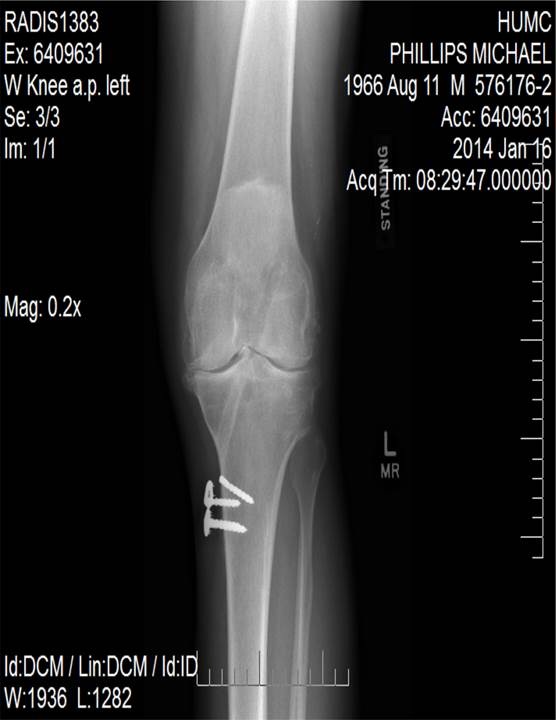

I am a 48 year old male. I used to race motorcycles in my early 20's and had an incident that required ligament surgery 5 years later that consists of a few plates and screws. After the OP years have gone by and arthritis is obviously accelerated a bit due to the injury. Since then I have had a series of surgeons that took care of me at different hospitals here in NJ and NYC. My family has been manufacturing implants and instrumentation for over 40 years. Being raised as a machinist, Engineering and president of operations in the medical manufacturing I know quite a bit about Products, hospitals all the way to FDA requirements.

Being very young for a total Knee Replacement (TKR) I new that I would have to ride out the discomfort as long as I could. Knees today have new technology but average there life at 20 - 25 years. After that you receive a Revision Knee that will last 5-10. After this technology is used they have to fuse your leg straight. I was now facing one of the most important decisions of my life. With this I had researched 3 different products (Zimmer, Stryker, Smith and Nephew) 3 hospitals, and 3 different surgeons one of which has been my surgeon for over 12 years. At each surgeon visit I had 15 questions about the product and the hospital they worked at as far as product success and Hospital procedures. After gathering all of this information 3 keys of information is why I made my decision. Smith and Nephew's current knee technology, Dr. Steven Haas's technique's (which I watched on line from an operation he did with explanations of techniques he uses and why) and the Hospital that represents him. After researching the hospitals success in a nearly NO RATE of infections was enough for me to decide. As you can imagine growing up in such a meticulous industry I am extremely tough on protocols and procedures which equals successful results. This hospital is the best I have seen on so many levels. The surgeons, anesthesiologists, nursing staff put me at so much ease I was actually glad I was there that day and had no worries for putting my Life in their hands. Living in NJ in no way makes it convenient to choose HSS as my hospital, but their is no way I or YOU should ever make such a decision out of convenience.